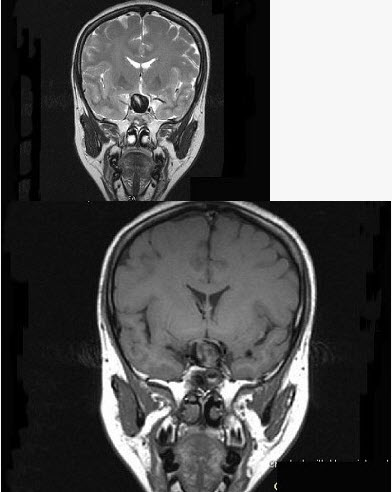

女,43岁,反复头痛10个月,CT检查如图,最可能诊断为()。

A、颅咽管瘤

B、垂体瘤

C、颈内动脉瘤

D、脑膜瘤

E、胶质瘤

正确答案:

C